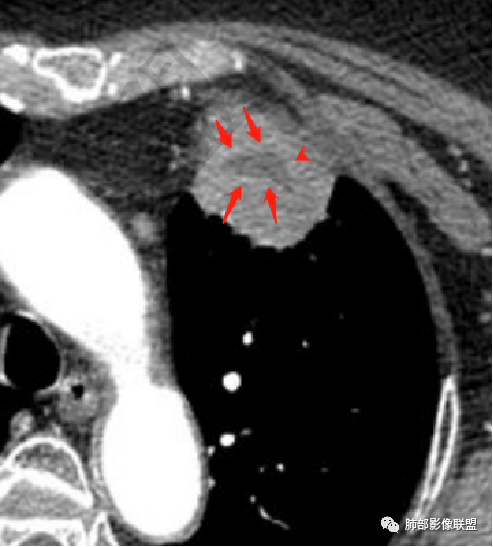

1、坏死区环形强化,指向慢性脓肿。

2、坏死区有血管,基本排除结核。

3、这个卫星灶,更进一步定了大方向,炎性。

※综上所述,看到这四幅图,基本能够准确诊断炎性※